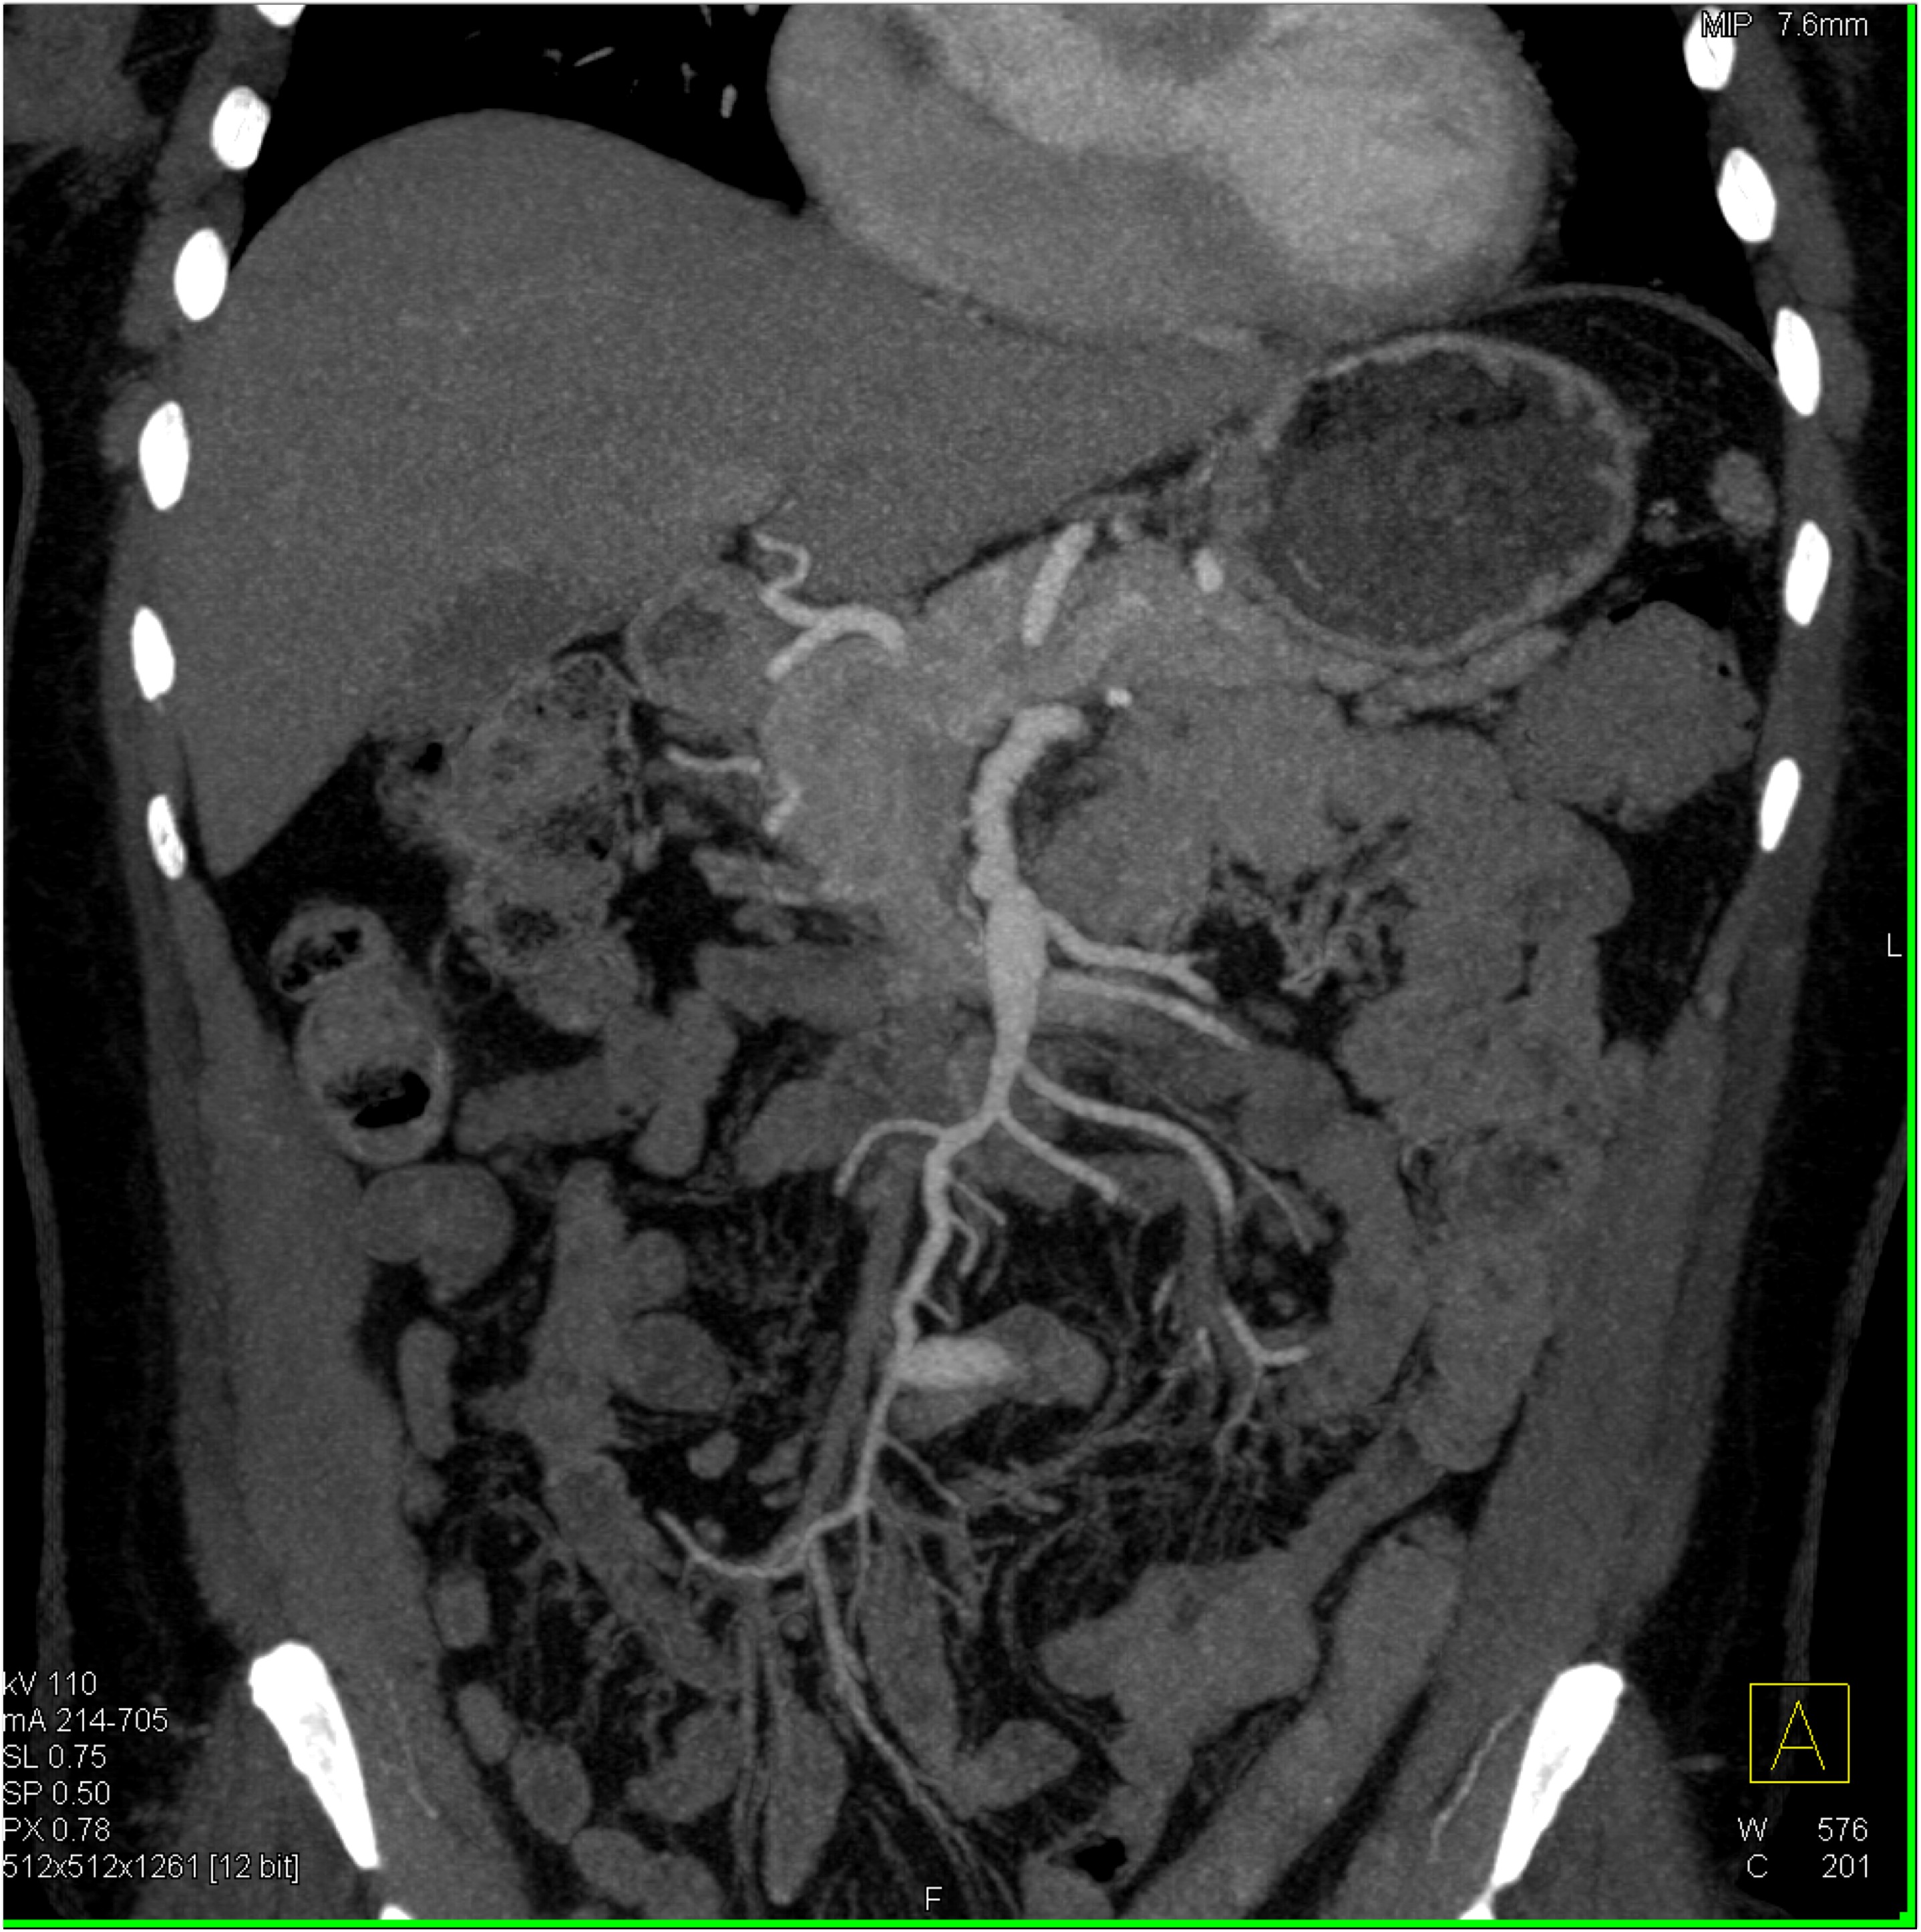

2) The differential diagnosis in this case includes?

FMD (fibromuscular dysplasia)

SAM (systemic arterial mediolysis)

Takayasu’s aortitis

all of the above